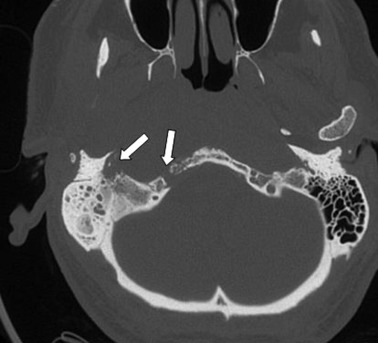

At Hospital Kuala Lumpur, our team will refer these patients to Hospital Angkatan Tentera Tuanku Mizan for HBOT. Typically, patients require 30 sessions per treatment. Post HBOT, a repeat HRCT temporal will be conducted to reassess disease progression.